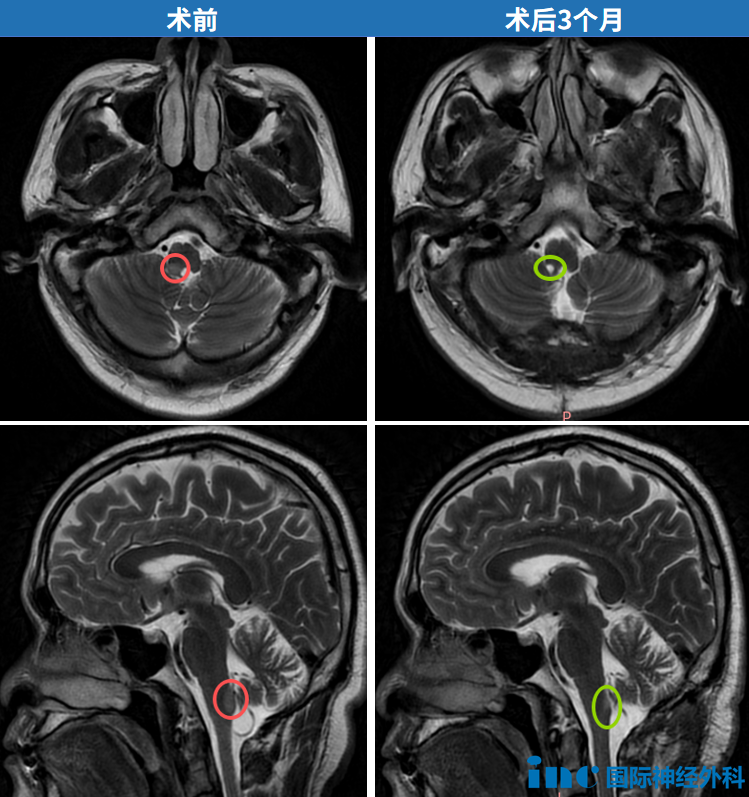

为何延髓位置会让人如此畏惧?而他们又是如何突破"手术禁区...